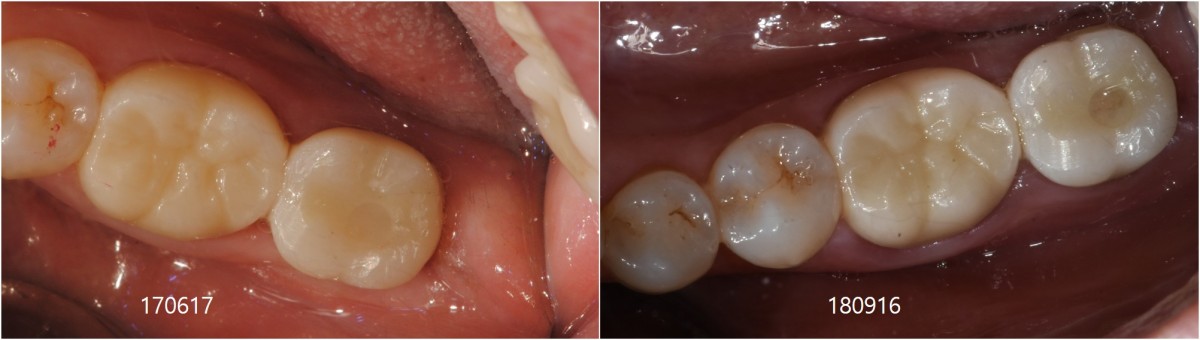

SIngle Implant - Immediate Placement, 8-year follow up

<CJ SBN> old female had mobility and pain when chewing in the lower molar